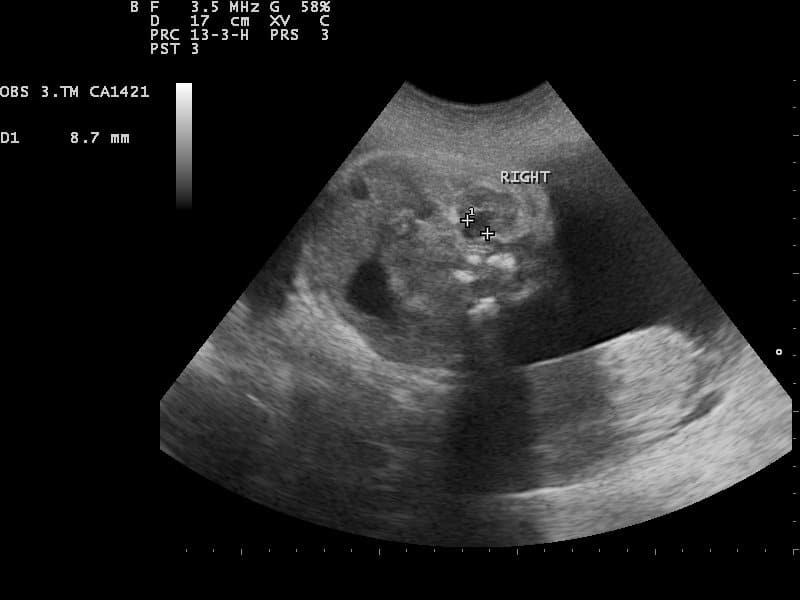

Fig 2 - Ultrasound image of normal fetal kidney. In cases of oligohydramnios, the kidneys should be assessed.

Ultrasound image of normal fetal kidney. In cases of oligohydramnios, the kidneys should be assessed.